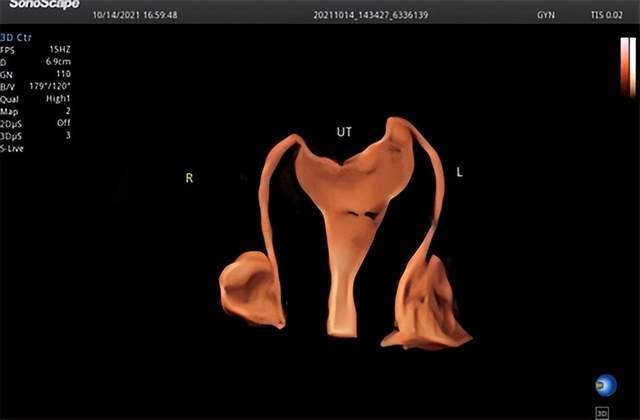

子宫输卵管造影是指在宫腔插管下向宫腔内注入超声微泡,通过四维超声,实时显示宫腔的形态、输卵管的走形以及盆腔的弥散情况,从而来评估双侧输卵管的通畅性,可同时观察子宫、输卵管和卵巢等是否存在病变。

子宫内膜三维成像